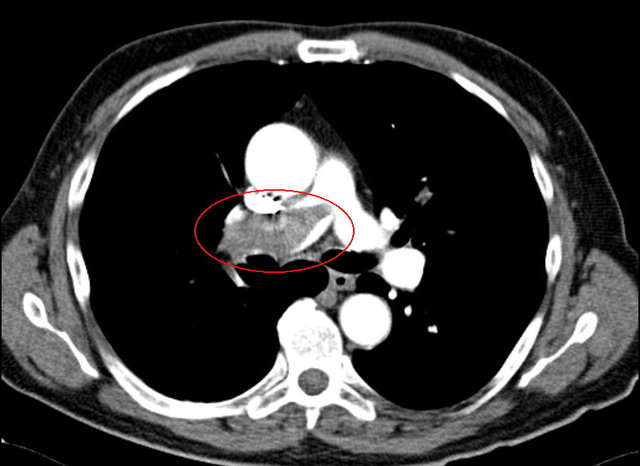

Bildgebung

Nachweis einer Lungenembolie mit Verlegung der rechten Pulmonalarterie. Gut sichtbar ist die Kontrastmittelaussparung im markierten Gefäß. © wikipedia.org/Bernd Brägelmann, mit freundlicher Genehmigung von Dr. Martin Steinoff, CC BY-SA 3.0